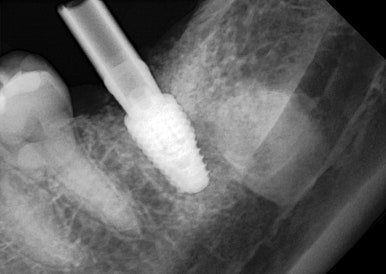

CT 분석 결과

✔ 잔존 뼈 상태 양호

✔ 신경 위치 안전

✔ 초기 고정 확보 가능

👉 그래서

**발치와 동시에 임플란트 식립 (즉시 임플란트)**을 진행했습니다.